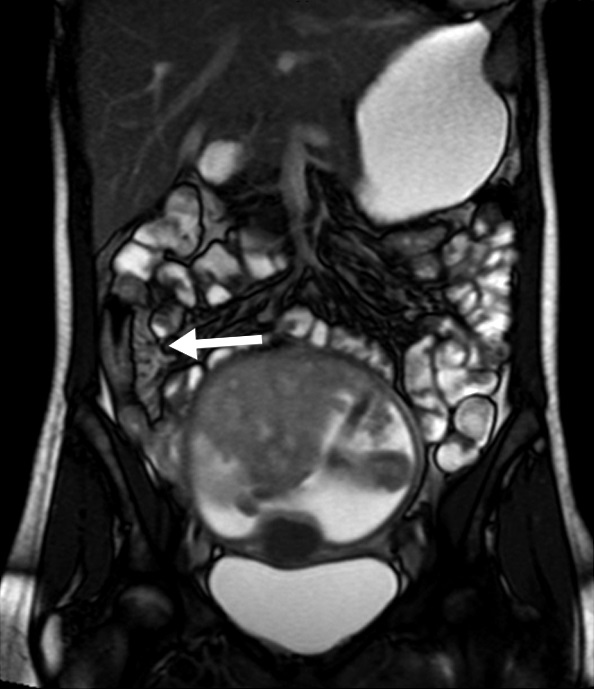

Figura 4

Paciente con enfermedad de Crohn

de 10 años de evolución, cursando

gestación de 13 semanas.

Secuencia eco de gradiente

coronal. Asas delgadas de paredes

engrosadas en la fosa ilíaca derecha,

se idenjpgican los vasos rectos

ingurgitados como estructuras

lineales perpendiculares a la pared

constituyendo el signo del peine

(flecha).